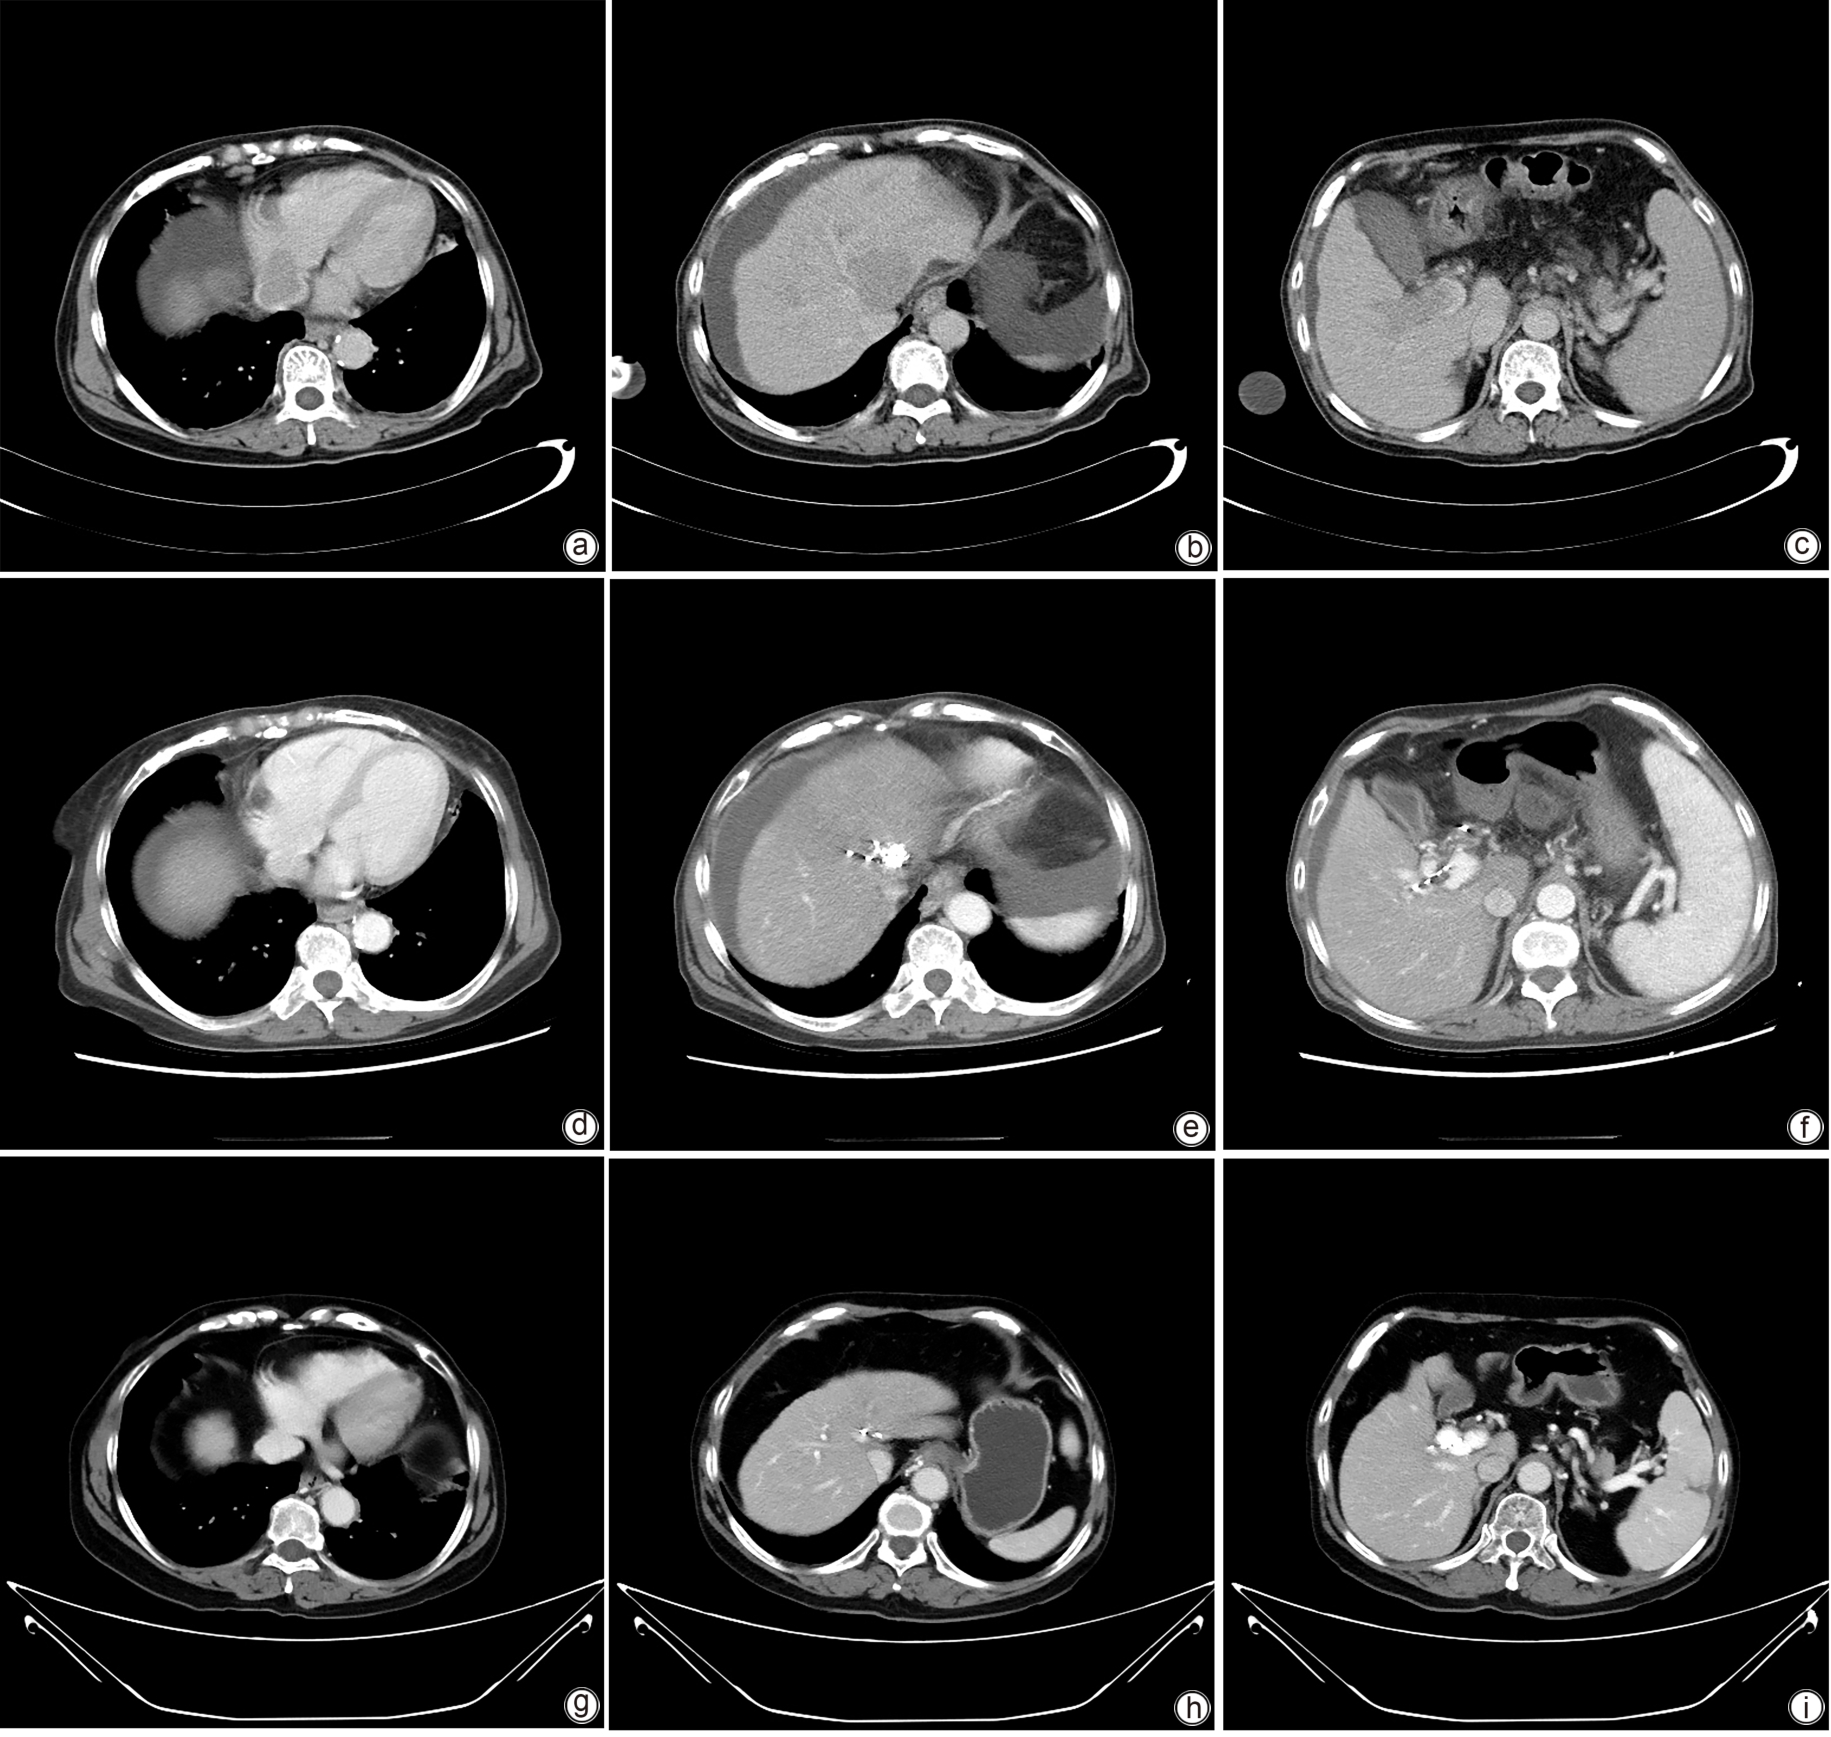

Large spontaneous splenorenal shunt embolization combined with anticoagulant therapy in treatment of portal vein thrombosis: A case report

Ju HUANG, Xiaoze WANG, Xuefeng LUO, Li YANG

2025, 41(8): 1639-1642. DOI: 10.12449/JCH250825

Abstract(504) HTML (172) PDF (3328KB)(67)

Abstract:

Portal vein thrombosis (PVT) is a common and severe complication in patients with liver cirrhosis, and alterations in portal hemodynamics are closely associated with the development of PVT. The presence of large spontaneous splenorenal shunt (SSRS) may lead to reductions in portal vein perfusion and blood flow velocity, which may compromise the anticoagulant effect on PVT. This article reports the treatment strategies of SSRS embolization combined with anticoagulant therapy that help to achieve complete recanalization of the portal vein; however, high-quality clinical studies are still needed to further validate and support the effectiveness of this strategy.